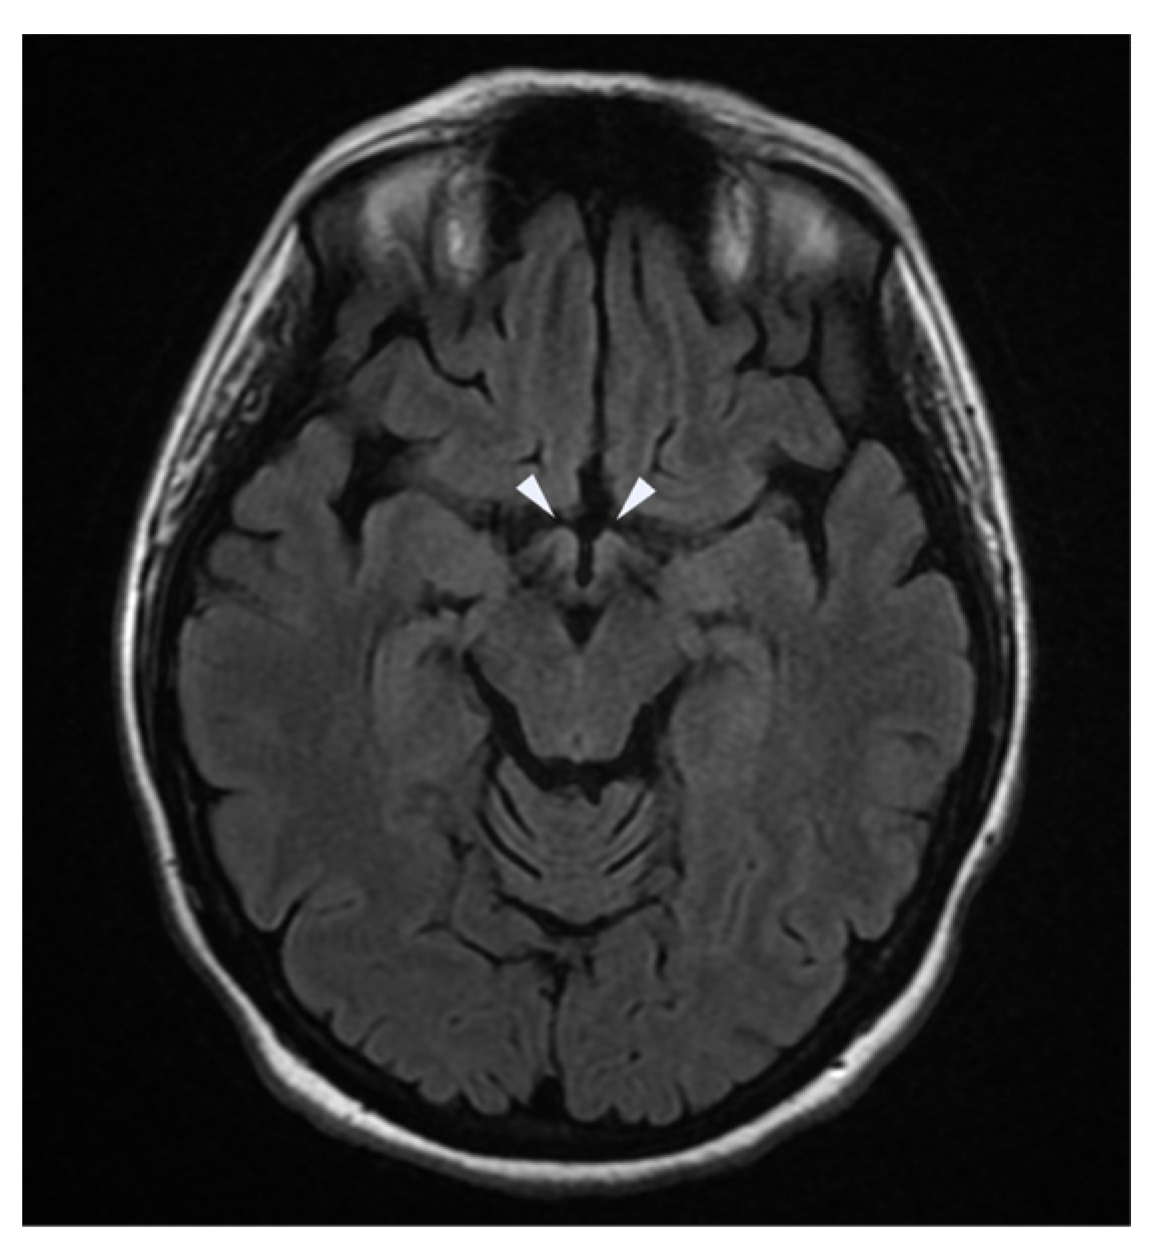

| Brain Imaging | MRI of the brain and spinal cord showed hyperintensity of:

|